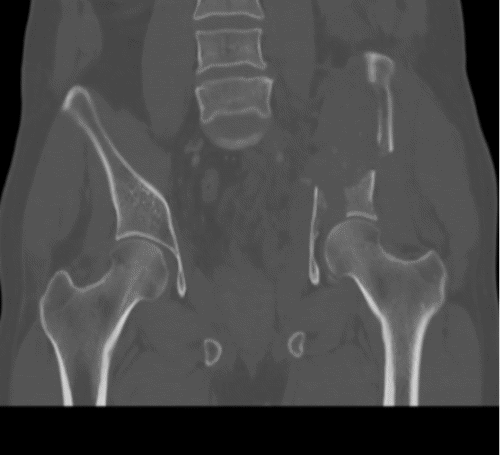

The patient's condition stabilized, and the pain was controlled with analgesia. CT showed no brain injury, but there were multiple left-sided comminuted rib fractures with displacement along the posterior and lateral aspects. In addition, it revealed the presence of hydropneumothorax; lung contusion with thoracic wall subcutaneous emphysema; right-sided mild pneumothorax; undisplaced fracture of the sternal body; herniation of the stomach into the pericardial cavity (Figure 1); no intraabdominal fluid or air and no solid organs injury; fracture of the transverse processes of the L3/L4 and L5 vertebrae; fractures of the left glenoid bone and left pelvic bone; multiple comminuted displaced fractures involving the iliac, acetabular, and pubic bones, with the displacement of the iliac bone fractures; right inferior pubic ramus nondisplaced fractures; and fracture of the left sacral alar and proximal left sacral segments (Figure 2).

Figure 2. Bone CT of Pelvic Fracture. A) Axial, B) Sagittal, and C and D) Coronal Views. Published with Permission

A) Axial View

C) Coronal View

D) Coronal View